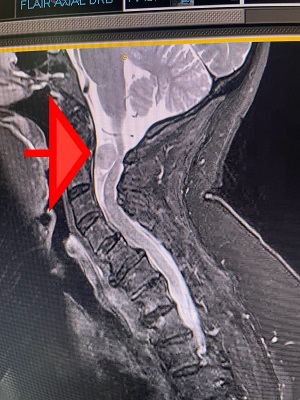

An MRI detected the benign 21mm spinal meningioma, which doctors explained as a non-cancerous tumour that arose from the membranes surrounding the spinal cord.

“This was an ultra-high risk surgery despite the tumour being benign,” he said. “There was limited view of the tumour because it was hidden by her spinal cord that had been stretched ribbon-thin.”

“The position and size of the tumour could have stopped the brain signals from travelling below her neck, paralysing her body from the chin down.”

Scan: Deborah's scan shows the location of the spinal tumour which was removed at Mater Hospital Brisbane.